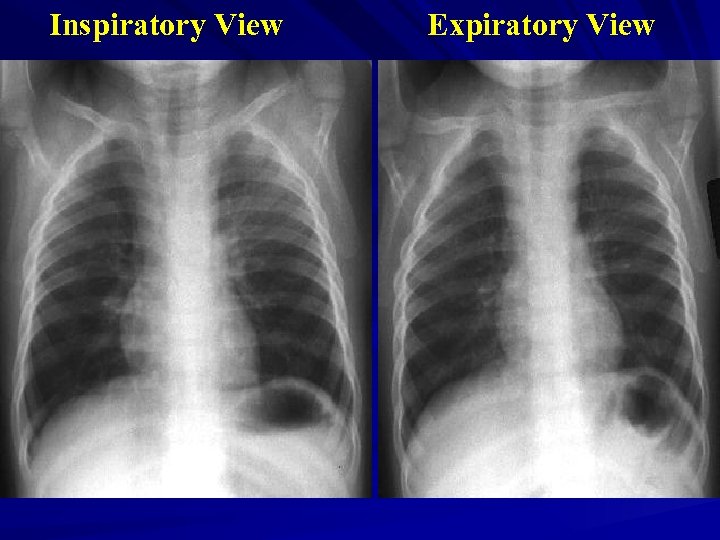

Inspiratory View Expiratory View

Investigations Xrays Ø Lateral neck Ø Chest – inspiratory, expiratory, decubitus views Expiratory views Overinflation (partial obstruction with inspiratory flow) Volume loss with mediastinal shift towards obstructed side (partial obstruction with expiratory flow) Atelectasis (complete obstruction)

Decubitus views Normal Smaller volumes and elevated diaphragm on side down Abnormal Hyperinflation or “normal” volumes in decub position If suspected … Need a bronchoscope to rule out or remove Foreign Body